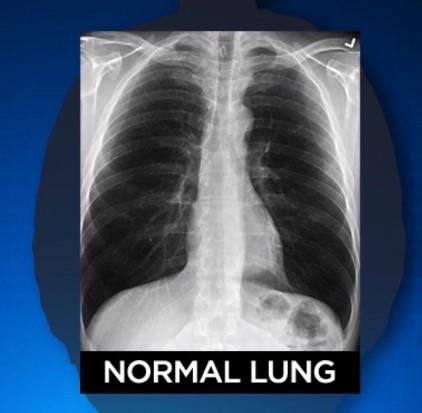

Kako bi pokazala kako kovid utiče na pluća, pokazala je snimke zdravih pluća, pluća pušača i onih osobe koja je preležala virus.

Rendgen zdrave osobe pokazuje veliku količinu crnog prostora, što znači da može da se udahne dosta vazduha.